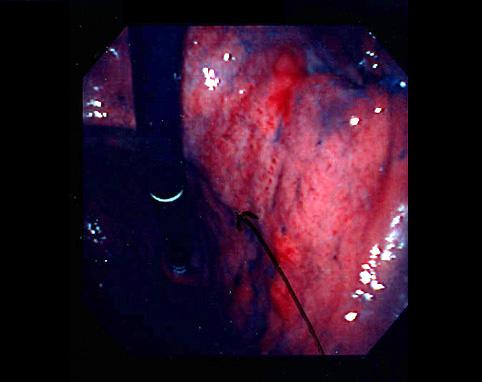

Criteria of Hist.ClassificationMalignant epithelial tumor/Adenocarcinoma

LocationStomach/Antrum

Technique, MethodEndoscopy

Macroscopic TypesType 3 Ulcerated type with infiltration/

Size40 -

Depth of Tumor Invasionserosa (adventitia)